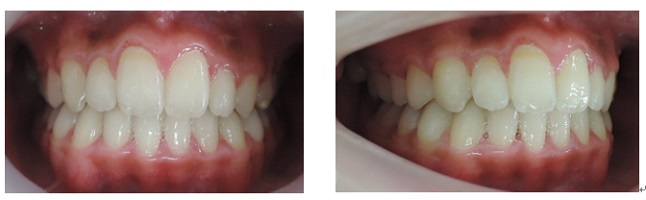

治療期間3年0か月で機能的で美しい咬み合わせが完成しました。

以下の上顎の症例では左右の第一小臼歯を抜かないと治療出来ないと説明があるはずです。しかし、当院での治療終了時には顎骨が拡大して綺麗に歯が並んでいます。

初診時 終了時

当院では拡大装置などを使用する事無く歯並びを綺麗に並べることが出来ます。